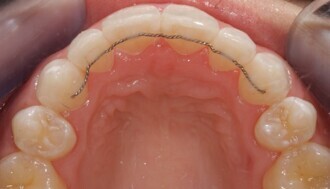

The Inman Aligner: Alignment, bleaching and bonding—A progressive approach to smile design (Part II)

The following article is Part II in a series discussing the use of the Inman Aligner as a tool for MICD.1 The first article (published in cosmetic dentistry...